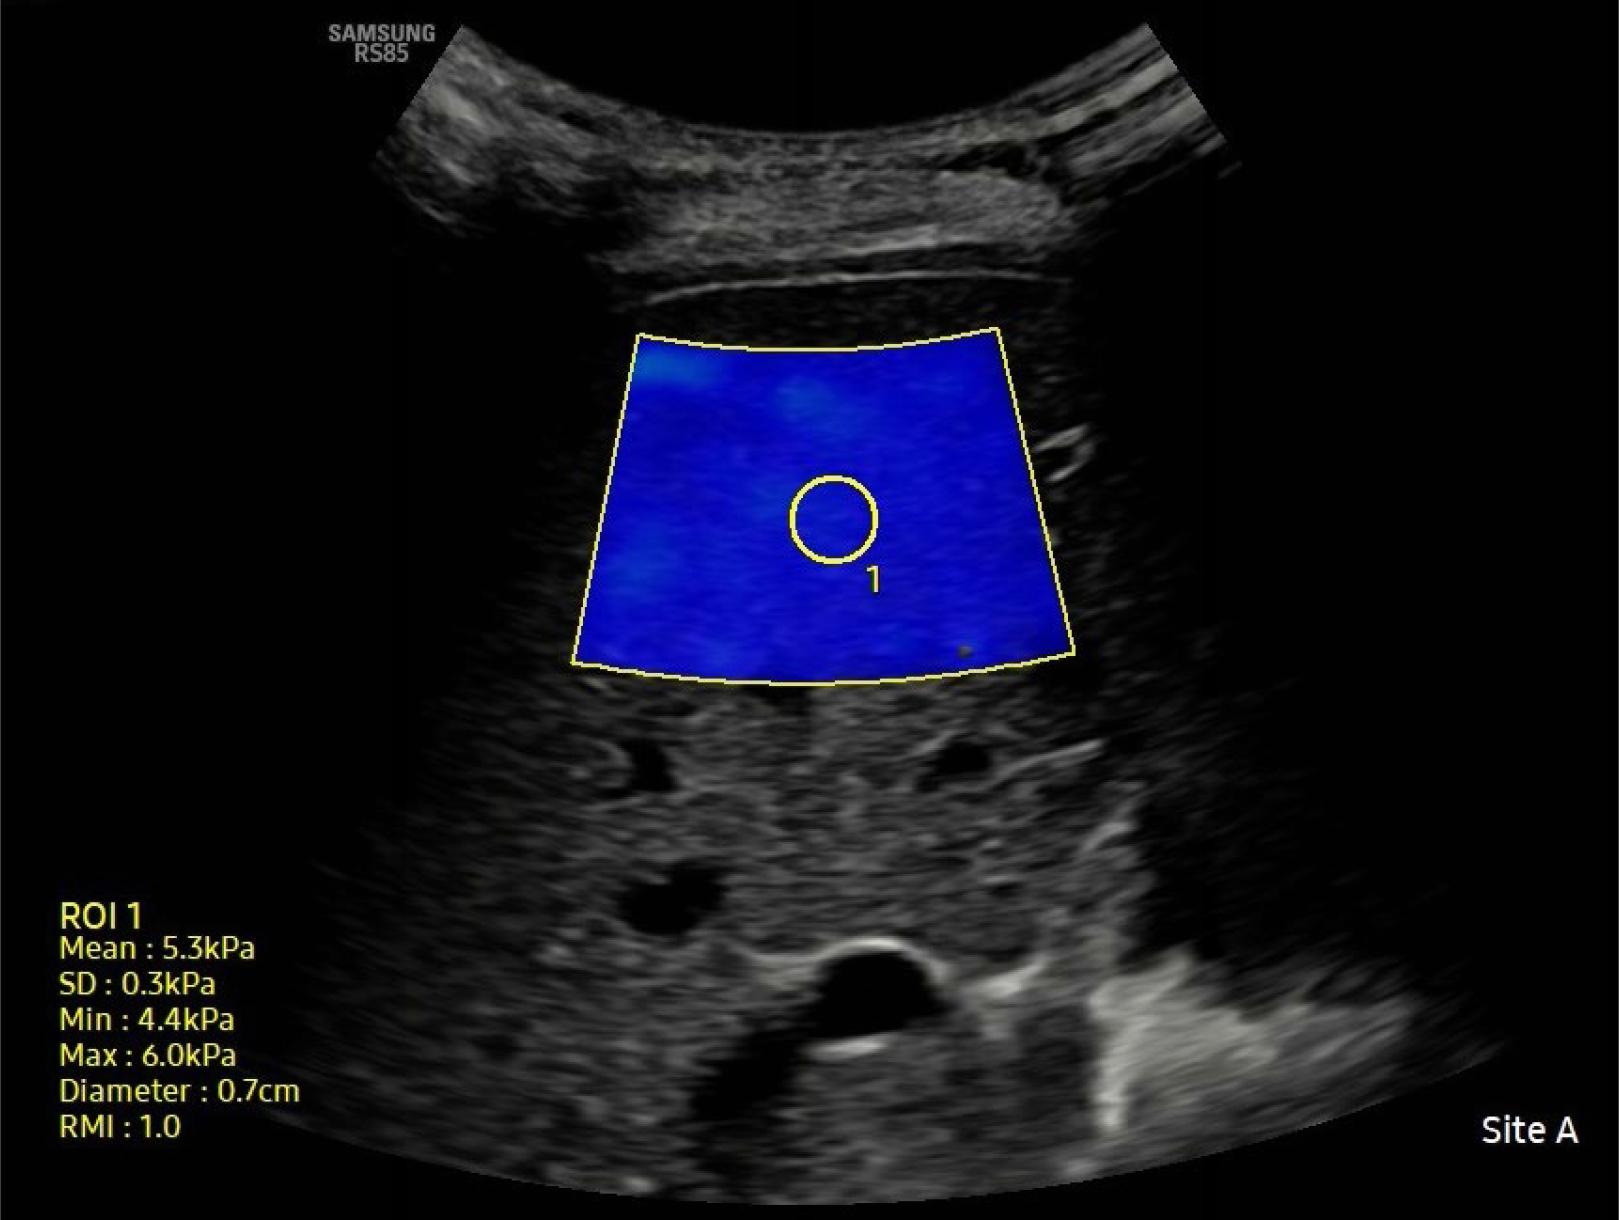

All SWE examinations were performed using a single device (RS85 Prestige, Samsung Medison Co. Ltd.) with a convex transducer (5 MHz) by the same radiologist. Patients were evaluated in a supine position with their right arm abducted. After instructing the patients to relax and remain in a neutral breathing position, the best intercostal space was used for assessment. SWE images were captured on grayscale ultrasound images within a rectangular region of interest (ROI) at least 2 cm from the liver capsule, taking care to avoid large vascular structures and bile ducts. Liver stiffness measurements were performed ten times. The median value was recorded. The results were expressed in kilopascals (kPa), accompanied by an autocalculated reliability measurement index to assess the confidence in each measurement. Since the reliability of measurements with RMI ≥0.8 and interquartile range (IQR)/median (Med) ≤30% was found to be high, these reference values were used in the study(17,18) (Fig. 1). HS was graded as 1, 2, and 3 (mild, moderate, and severe) based on findings commonly assessed in USG, such as liver parenchymal structure and echogenicity, and the clarity of the diaphragm and hepatic vessels(19). The midclavicular line was determined to measure the size of the liver.

SWE images were generated on gray-scale images within a region of interest (ROI) at least 2 cm away from the liver capsule, with particular attention given to avoid large vascular structures and bile ducts. At the bottom right, liver stiffness values (mean, SD, min, max), ROI diameter (diameter), and reliability measurement index (RMI) are shown to assess the reliability of each measurement